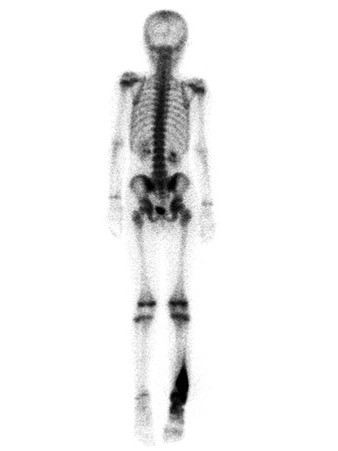

На этой остеосцинтиграмме (вид сзади) определяется повышенное накопление радиоизотопа в правой голени подростка, что характерно для активно растущей опухоли кости. Вид симметричных областей накоплений в коленных, плечевых и запястных суставах типичен для нормального развития скелета